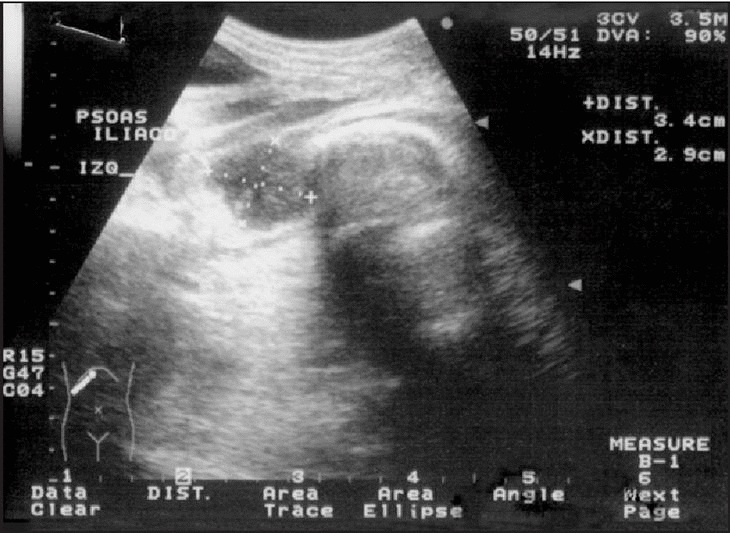

La radiografía de tórax mostró opacidad del seno costofrénico izquierdo. La ecografía abdominal permitió apreciar la existencia de hepatomegalia con leve aumento de la ecogenicidad compatible con esteatosis, fibrosis o granulomatosis; esplenomegalia con múltiples imágenes focales hipoecoicas; vesícula de paredes engrosadas, alitiásica; ascitis abundante, tabicada, y derrame pleural izquierdo. El páncreas y riñones eran normales. En ambas fosas ilíacas se visualizan imágenes hipoecoicas de 145 x 62 x 26 mm a la derecha y 34 x 29 x 22 mm del lado izquierdo compatibles con abscesos del músculo psoas (figs. 1 y 2).

Figura 2. Ecografía abdominal con imagen hipoecoica en músculo psoas ilíaco izquierdo compatible con absceso.